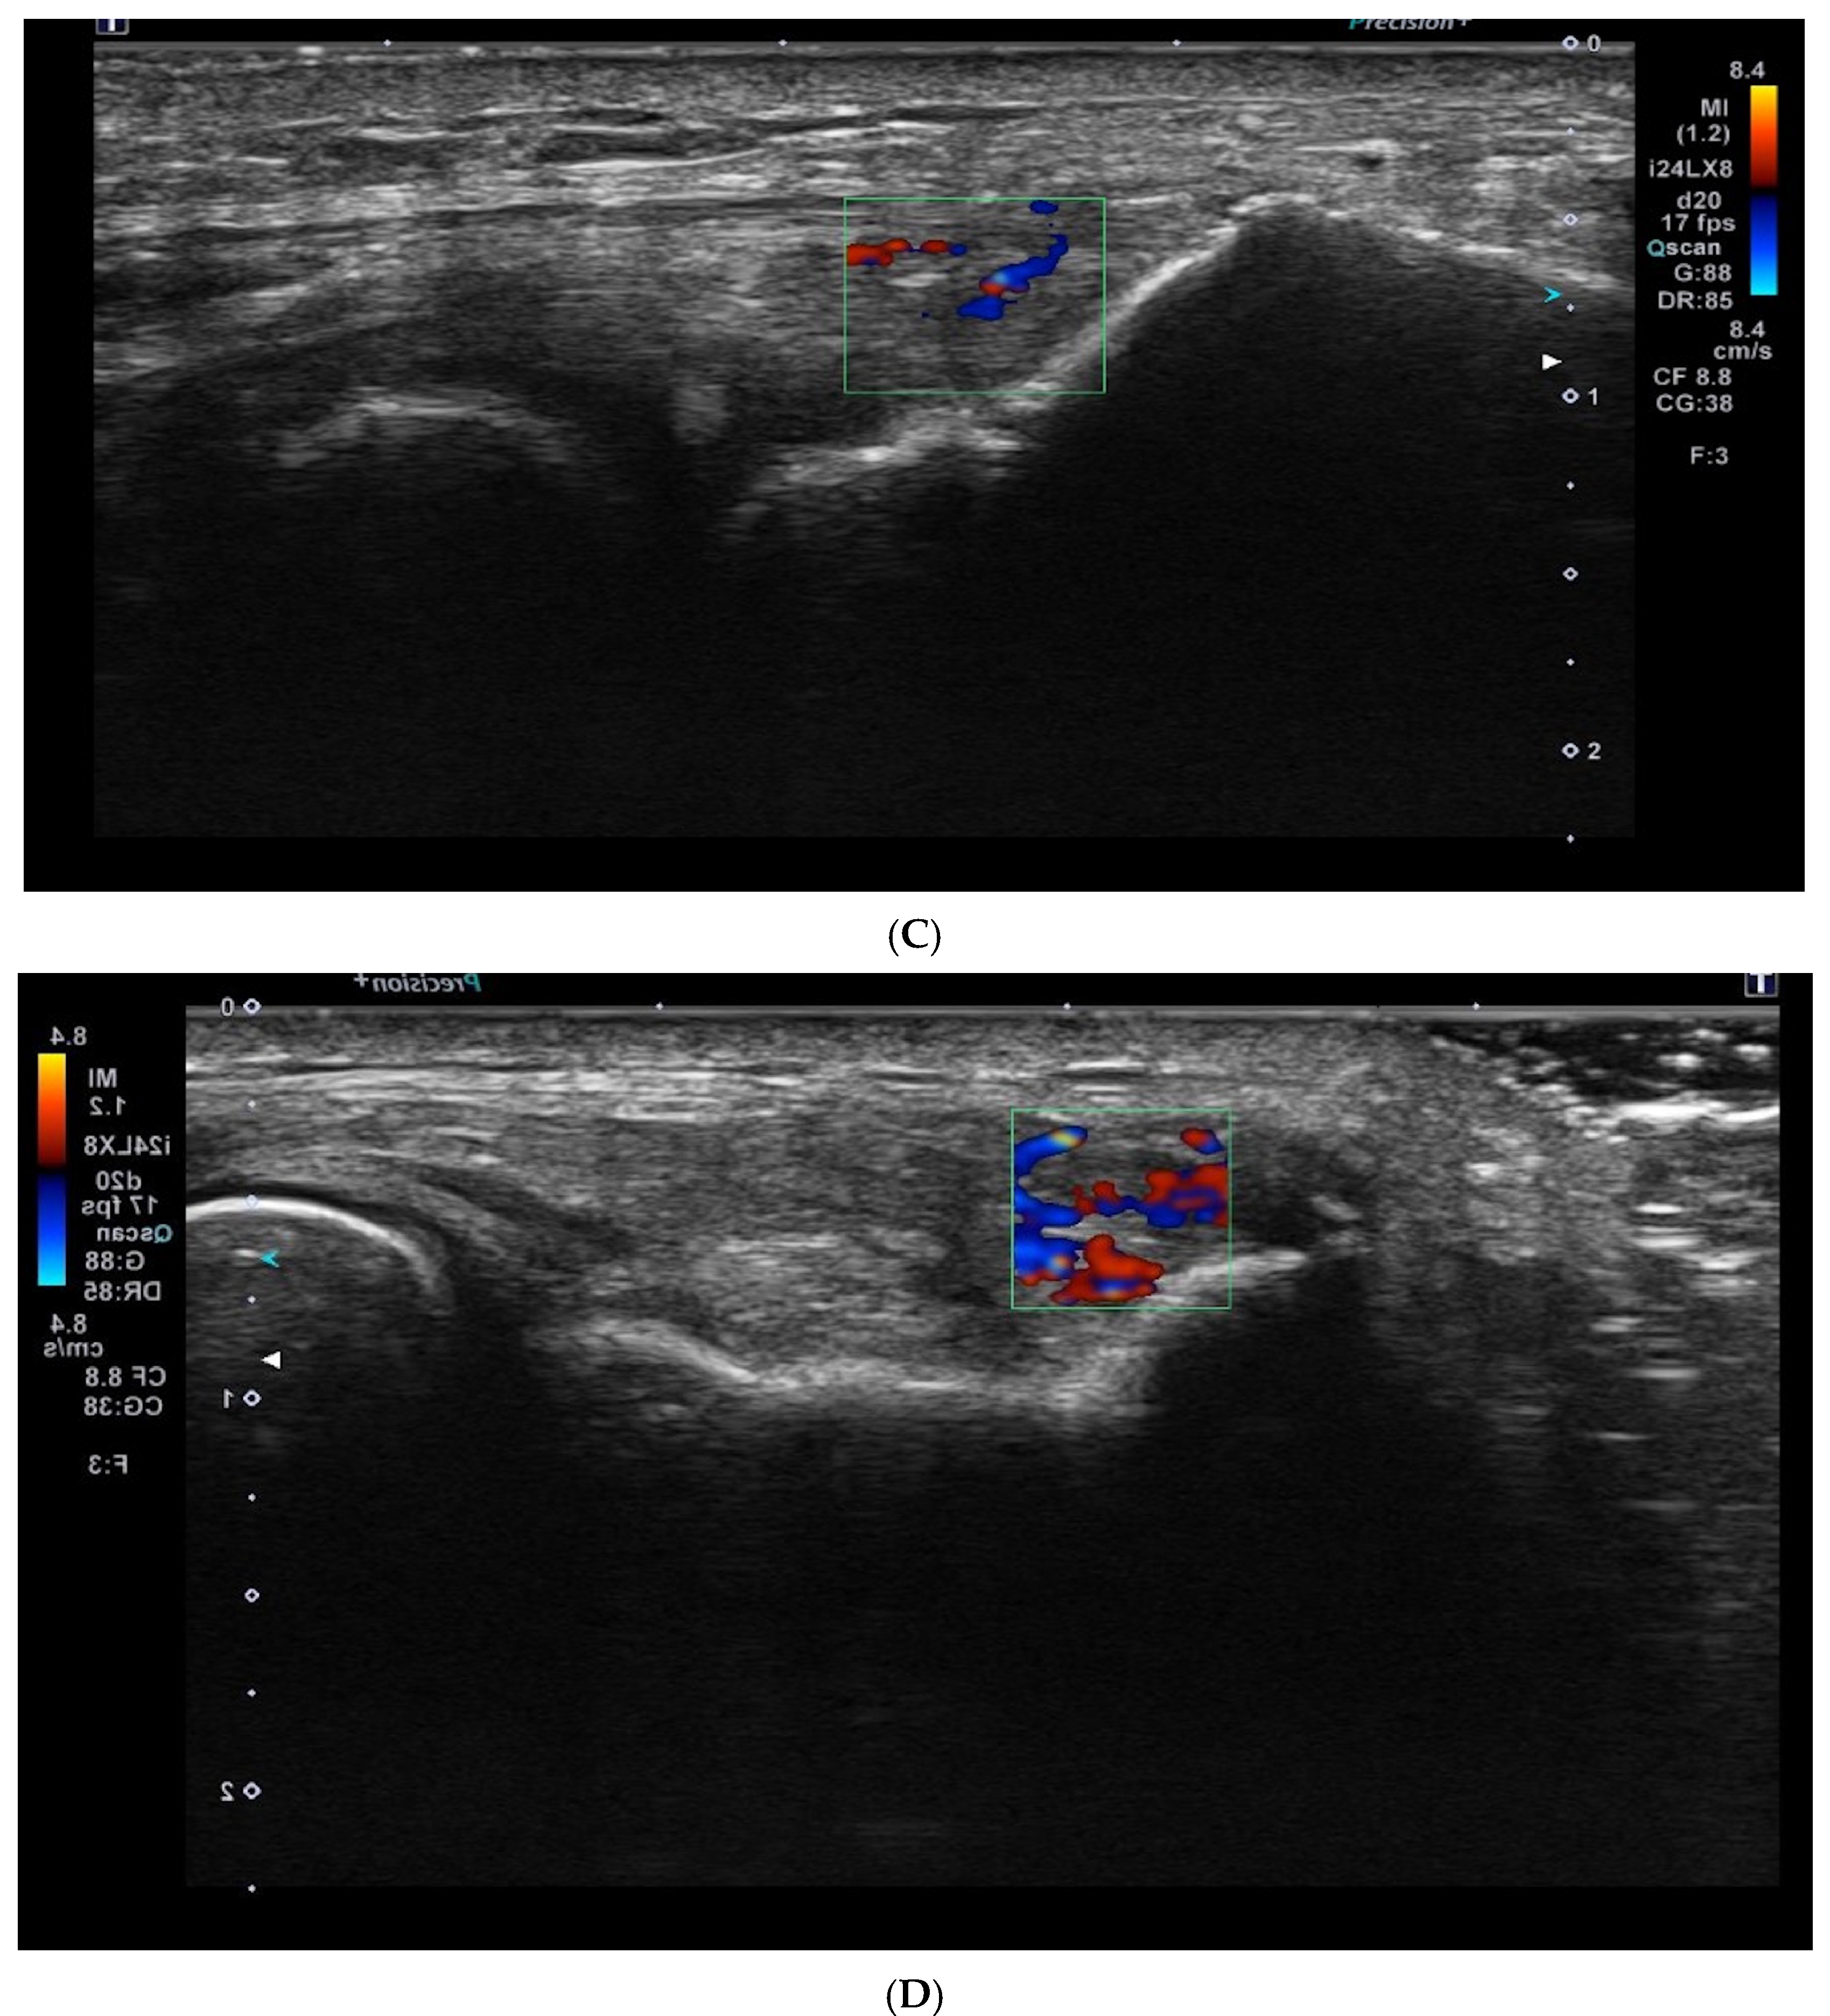

Superb microvascular imaging (SMI) was assessed alongside Doppler ultrasonography (USG) as described in the literature, allowing for a more quantitative evaluation of vascularity [21] (Figure 3).

Figure 3.

Superb microvascular imaging (SMI) in USG for lateral epicondylitis. The SMI technique enhances visualization of microvascular structures with high sensitivity, distinguishing low-velocity blood flow that may be associated with tendon inflammation and neovascularization.

The mean Doppler USG grades at baseline were 2.9 ± 1.1 in the PRP group, 1.9 ± 1.5 in the saline group, and 2.2 ± 1.4 in the glucocorticoid group, which decreased to 2.1 ± 1.4, 1.7 ± 1.4, and 1.4 ± 1, respectively, after treatment. These changes showed no correlation with clinical score improvements. Consequently, we utilized the SMI method, which is more sensitive and specific than Doppler USG grading for lateral epicondylitis, providing a more accurate demonstration of vascularity at the myotendinous junction [21].

In our study, the SMI technique was utilized for the first time in the follow-up after injection, differing from previous literature. The percentage change in SMI measurements was not significant among the glucocorticoid (9.8 ± 7.8 from 9.8 ± 9.3), saline (10.24 ± 8.4 from 9.3 ± 7.5), and PRP (7.06 ± 6.6 from 12.4 ± 6.9) groups.